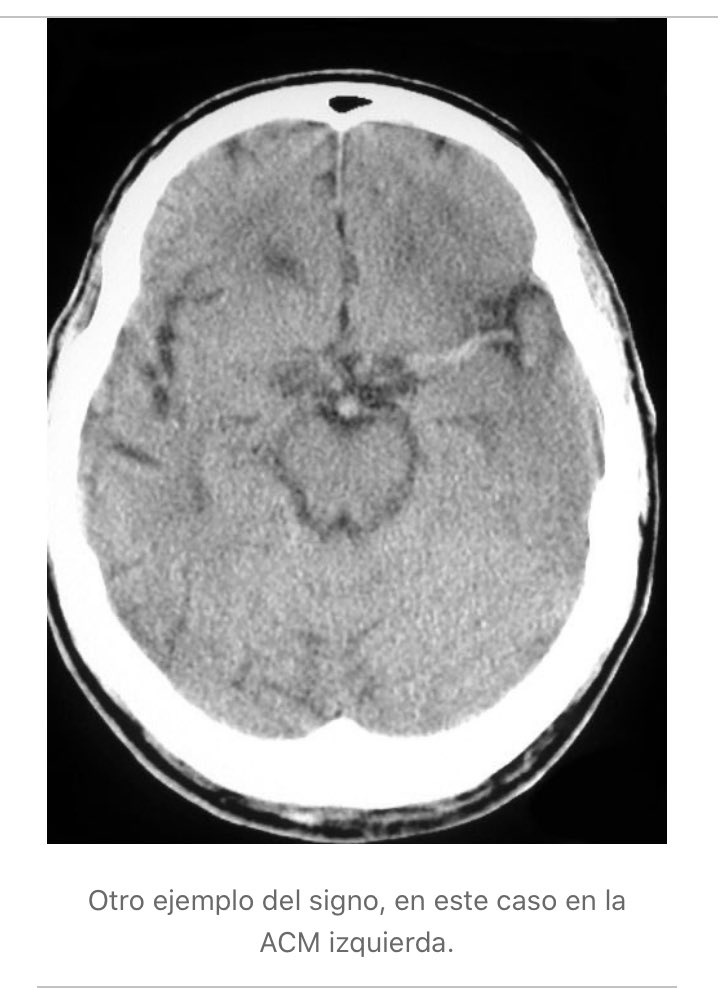

Se Observa El Signo De La Cuerda Dado Por La Hiperdensidad De La Download Scientific Diagram

Multimedia En Medicina 34 Signo De La Cuerda Interconsulta On Line